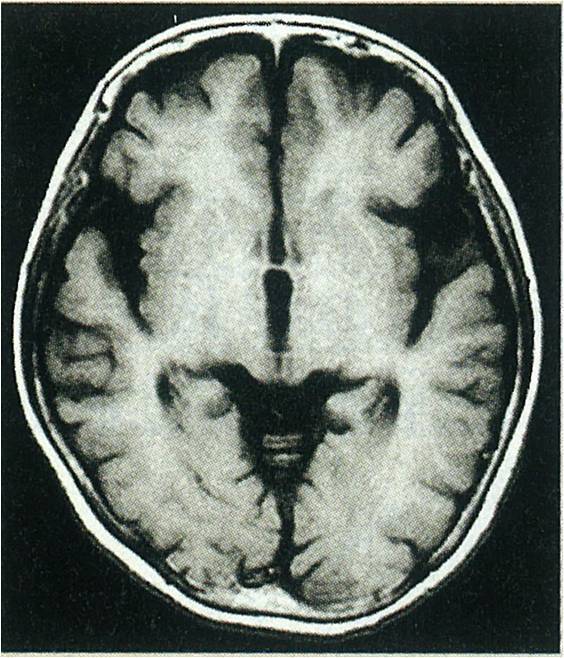

でも脳は覚えてるんやなー

夢でも鮮明にあの時の脳のリセット具合を体験してしまうから脳ってすぎょい